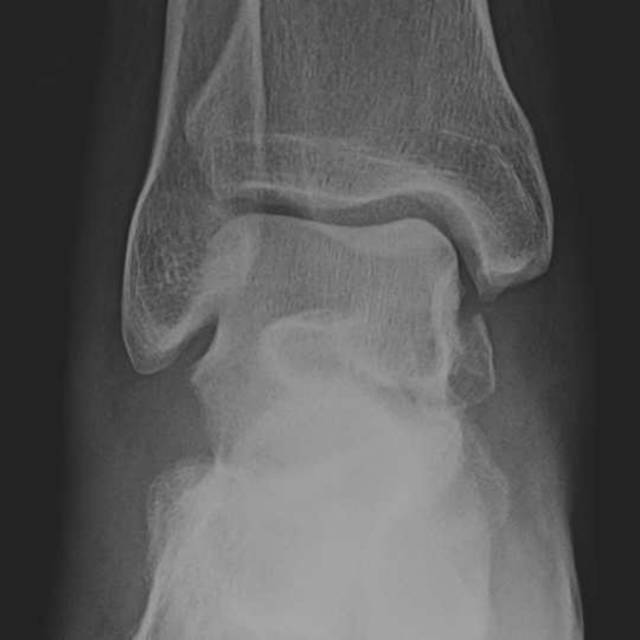

在脚踝处,必须警惕超出投照视野(图4)的足部腓骨骨折的可能性和足部骨折的可能性。例如,Maisonneuve骨折是一种旋前 - 旋转损伤,伴有远端胫腓骨间继位断裂和近端腓骨骨折[19]。了解骨折模式与相关的损伤机制模式至关重要,特别是在踝关节[20]。

图。4A-28岁女子在地面跌倒后。A,踝关节的斜视图显示继发性加宽和微小的内侧踝撕裂性骨折。B,近侧腿的侧视图显示倾斜的近端腓骨骨折,构成Maisonneuve骨折。